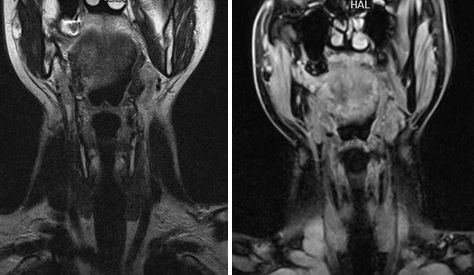

Онкологический процесс на томограммах щитовидной железы

Метастазы на снимках МРТ шеи